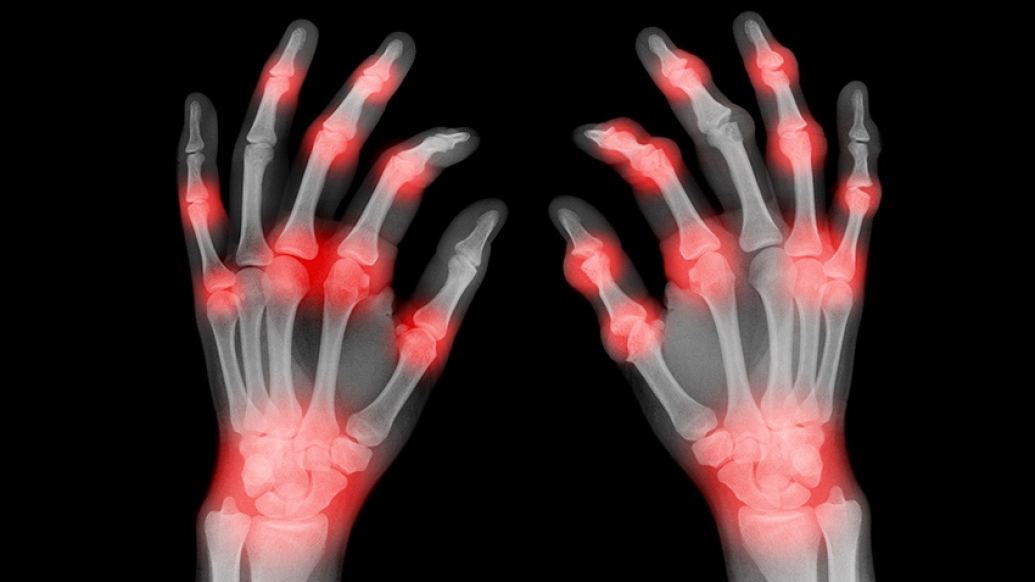

hands of xray finfers with red spots

Aches and pains in your hands or wrists, or sore, swollen fingers could signal a condition known as arthritis.

All types of arthritis can cause pain, swelling and stiffness anywhere in the body, but when it affects the hands, wrist or fingers, it can be particularly difficult, preventing you from doing daily activities. In the most severe cases, arthritis can cause loss of function.